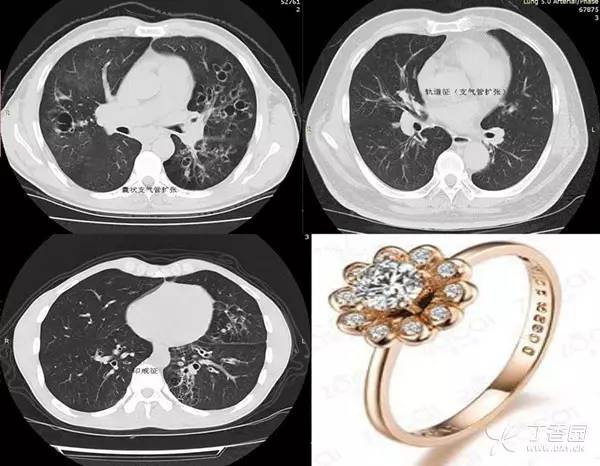

印戒征的影像表现由一个小的圆形软组织密度影和一个圆形低密度区的较大的环形软组织密度影相连而成,形似印戒。

软组织密度环代表扩张的支气管,其内低密度为扩张支气管内所含的气体,小圆形软组织密度影代表与扩张支气管伴行的肺动脉。

受累的支气管常见于中等管径的支气管,因为主、叶及段支气管软骨较硬较厚,对扩张的抵抗力较大,而在严重支气管扩张的患者中,远端小支气管常有闭塞,数量减少,故仅有中等大小的支气管才能明显的扩张。

印戒征是支气管扩张的 CT 表现,它是支气管壁弹性组织和肌肉组织破坏而导致的局部支气管不可恢复的异常扩张,是受累支气管多种病理过程共同的最终结果。支气管扩张的病理改变主要是管腔扩张和管壁增厚。